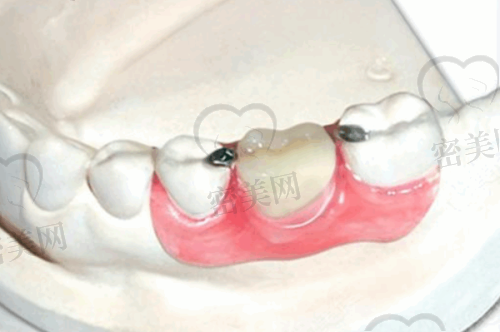

牙齿种植:采用精良的种植技术和优质的种植体,为缺失牙患者提供解决方案。医生会根据患者的口腔情况和身体状况,制定个性化的种植方案,确保种植成效的稳定性和持久性。